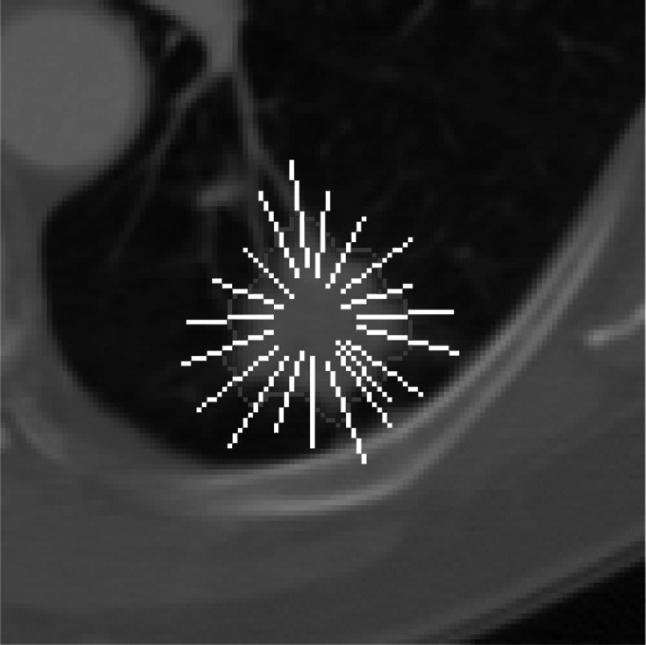

3D Margin Sharpness Features (MSF). Following a model partially proposed by Xu et al. [41], we extracted 12 MSF from the intensities of transition between intranodular and perinodular zones (Fig. 4). Xu et al. [41] defined the calculation of these features in two characteristics: (1) measurements of difference in intensity between the pixels from intranodular and perinodular zones; and (2) measurements of pixel intensity transition over the edge of the nodule. Hence, these features were obtained by generating orthogonal lines at the edge of the nodule, where the pixel values contained in these lines were stored in an array of gray levels, then, this array was sorted in ascending order, and the statistical features were calculated based on its content.

Fig. 4.

Orthogonal lines drawn over the edge of the pulmonary nodule